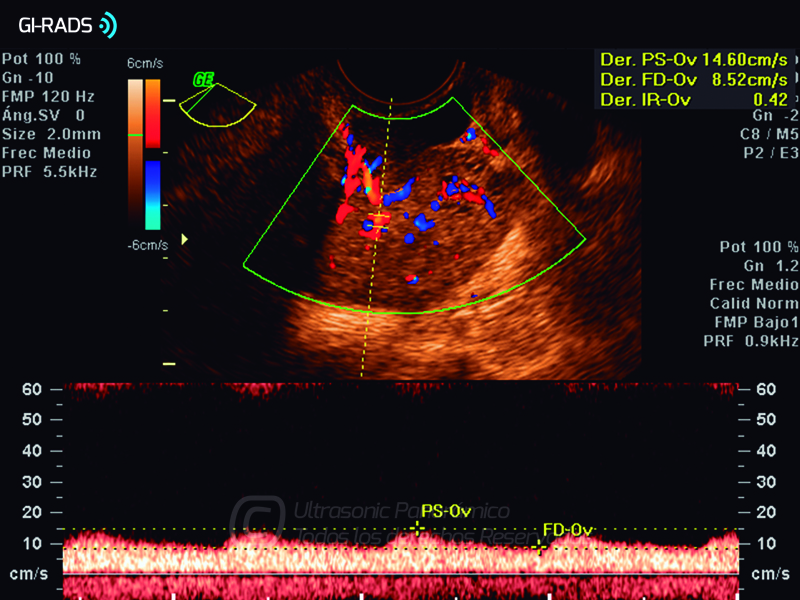

Cáncer Anexial – Flujo Abundante

• Cáncer Anexial – Flujo Abundante